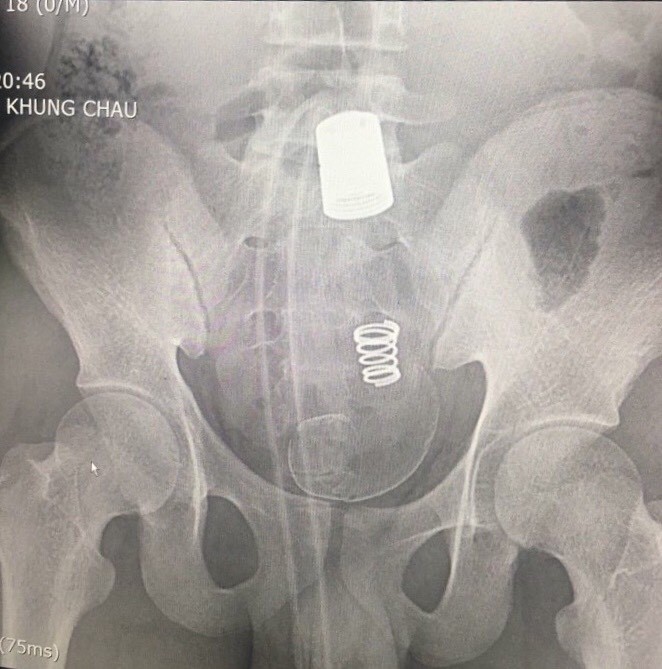

Hình ảnh dị vật trên phim chụp X-quang. - Ảnh: Dân trí |

BS Vinh cho biết, qua thăm khám hậu môn cho thấy dị vật hình ống silicon, rất chắc và không thể lấy ra được qua đường hậu môn. Dị vật cũng gây nên tình trạng chảy máu niêm mạc đường ruột.

Vì thế, sau khi hội chẩn, các bác sĩ quyết định phẫu thuật lấy dị vật cho bệnh nhân. Kíp phẫu thuật đã mở bụng, mở đại tràng sigma lấy được cả đoạn vòi nước và đầu xả dài khoảng 45 cm.